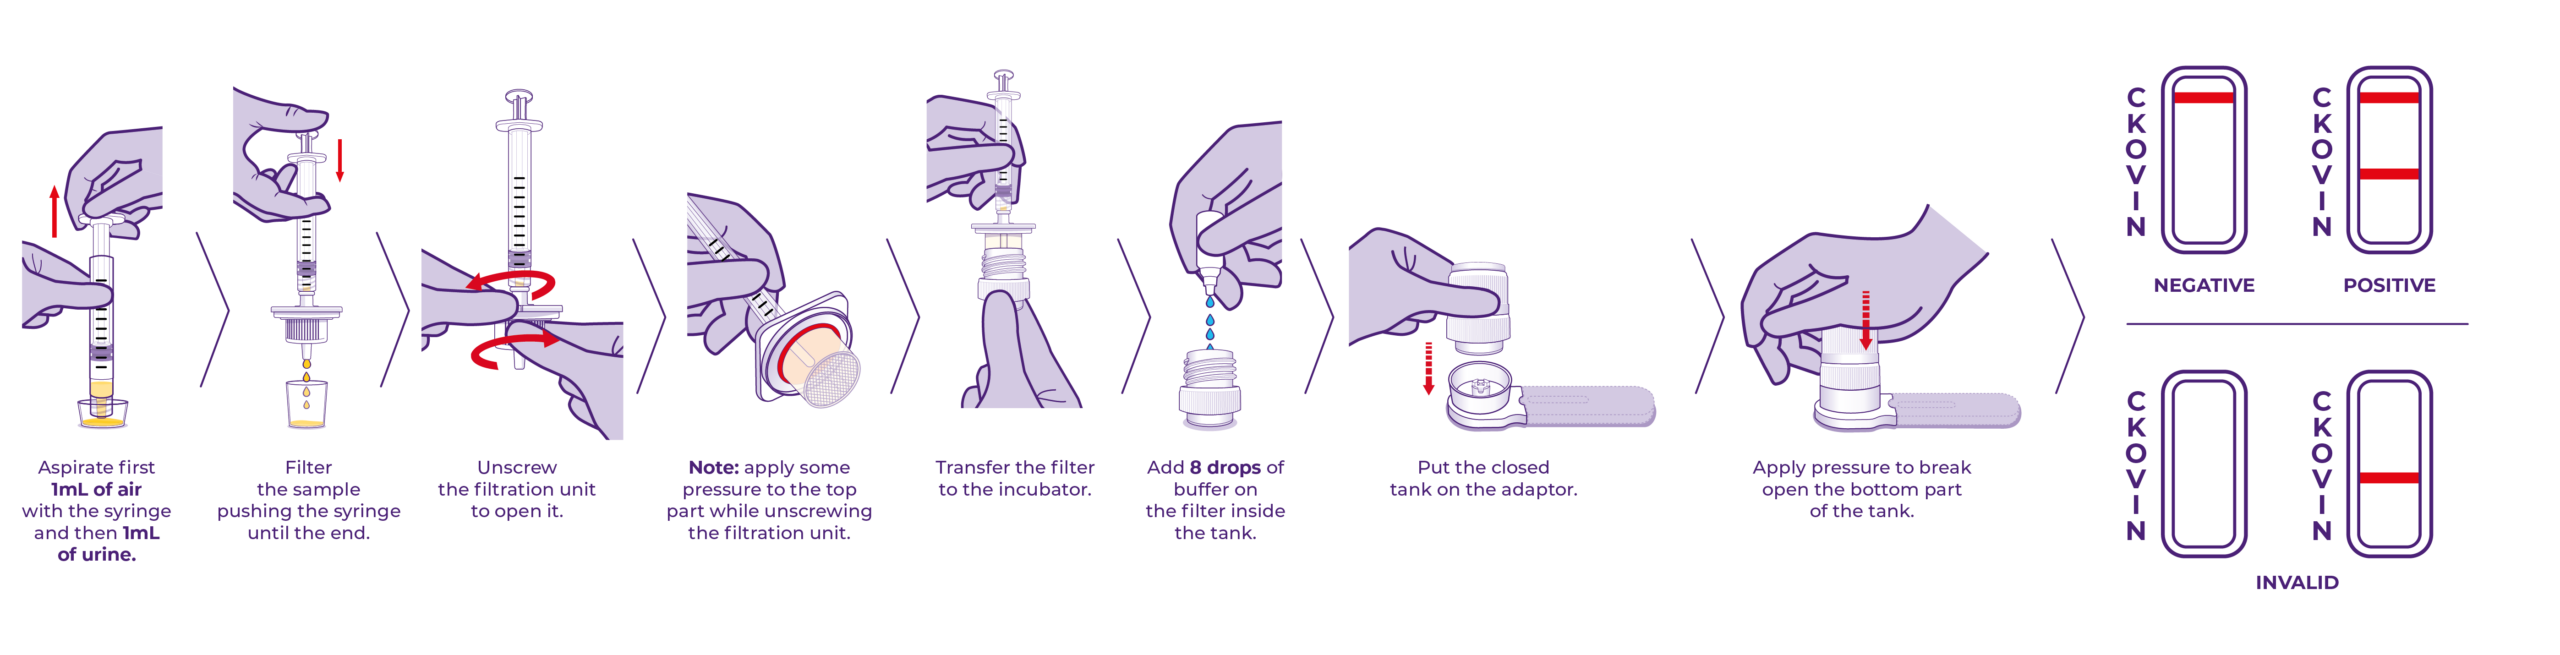

NG-TEST® Vet are easy-to-use and allows to have results in 15 min bacteria sample without any instrument.

NG-TEST® Vet Direct ESBL is a ready-to-use kit comprising a sample preparation device (DirecTool) and a rapid test in cassette format (CTX-M Multi) designed for the detection of the main extended-spectrum β-lactamase (ESBLs).

The NG-TEST® Vet is a rapid immunoassay for the detection of groups 1, 2, 8, 9 and 25 CTX-M β-lactamases in Enterobacterales extracted irectly from urine sample.

NG-TEST® Vet Direct CRE NG-TEST® Vet test are easy-to-use and allows to have results in 15 min bacteria sample without any instrument.

NG-TEST® Vet Direct CRE is a ready-to-use kit comprising a sample preparation device (DirecTool) and a rapid test in cassette format (CARBA-5) designed for the detection and differenciation of the five most common carbapenemase families.

The NG-TEST® Vet Direct CRE is a rapid multiplex immunoassay for the detection of one or more of the five common types of carbapenemase enzymes (KPC (K), OXA-48-like (O), IMP (I), VIM (V), NDM (N) in Enterobacterales and Pseudomonas aeruginosa extracted directly from urine sample.